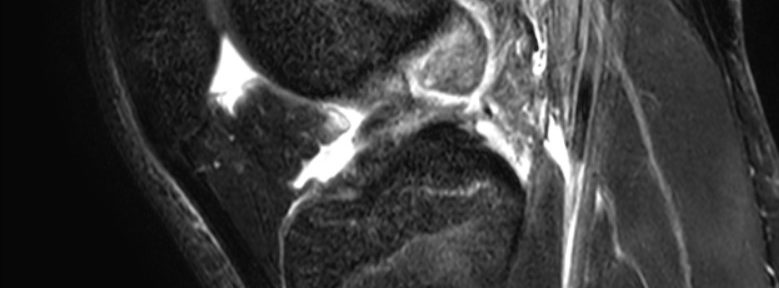

[Case 39] A 36-Year-Old Male Skier with a Complete ACL Tear Who Achieved Natural Healing through Evo-Devo Exercises: A Case Report

This page presents a case report of a 36-year-old male …